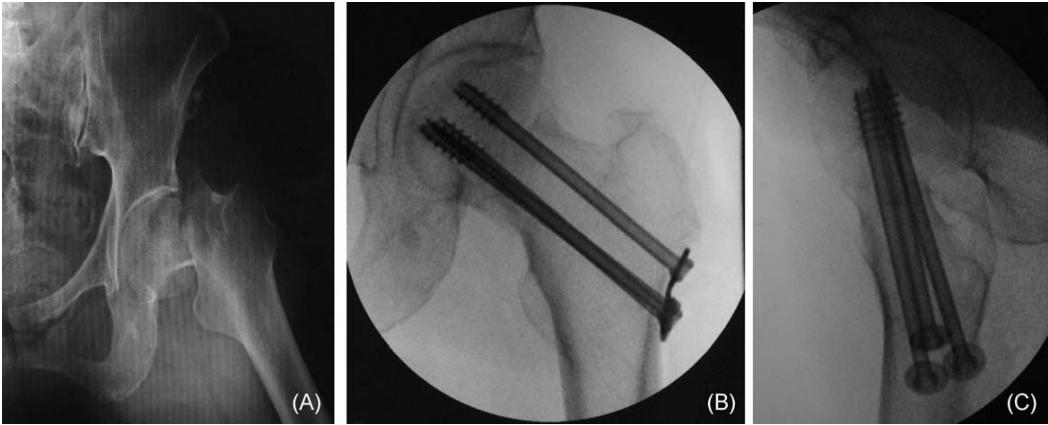

应用股骨颈骨折的微创伤复位程序,患者在全身麻醉下取仰卧位。必须首先通过触诊定位股动脉。克氏针或斯氏针在大腿近端的插入点位于股动脉外侧1.5-3厘米处。应仔细准备导丝的插入角度。首先在术中透视引导下,将一或两根克氏针或斯氏针经皮穿过软组织插入股骨头,针尖方向略偏外侧。再次进行触诊以确认股骨神经血管束完好无损。将克氏针或斯氏针垂直插入股骨头中部1/2至2/3处,股骨头软骨下骨下方超过1厘米。将针插入股骨头,深度约为股骨头直径的1/2(图3)。

图 3. 前后位X光片(A)显示克氏针插入股骨头中部1/2处,股骨头软骨下骨下方超过1厘米。侧位X光片(B)显示克氏针插入股骨头,深度约为股骨头直径的1/2。

如果患者有骨质疏松症,则应将克氏针插入超过股骨头的2/3,以确保良好的把持和控制。使用术中C臂透视来相应地指导和调整克氏针的方向和位置。然后,将股骨头旋转至其原始移位状态。